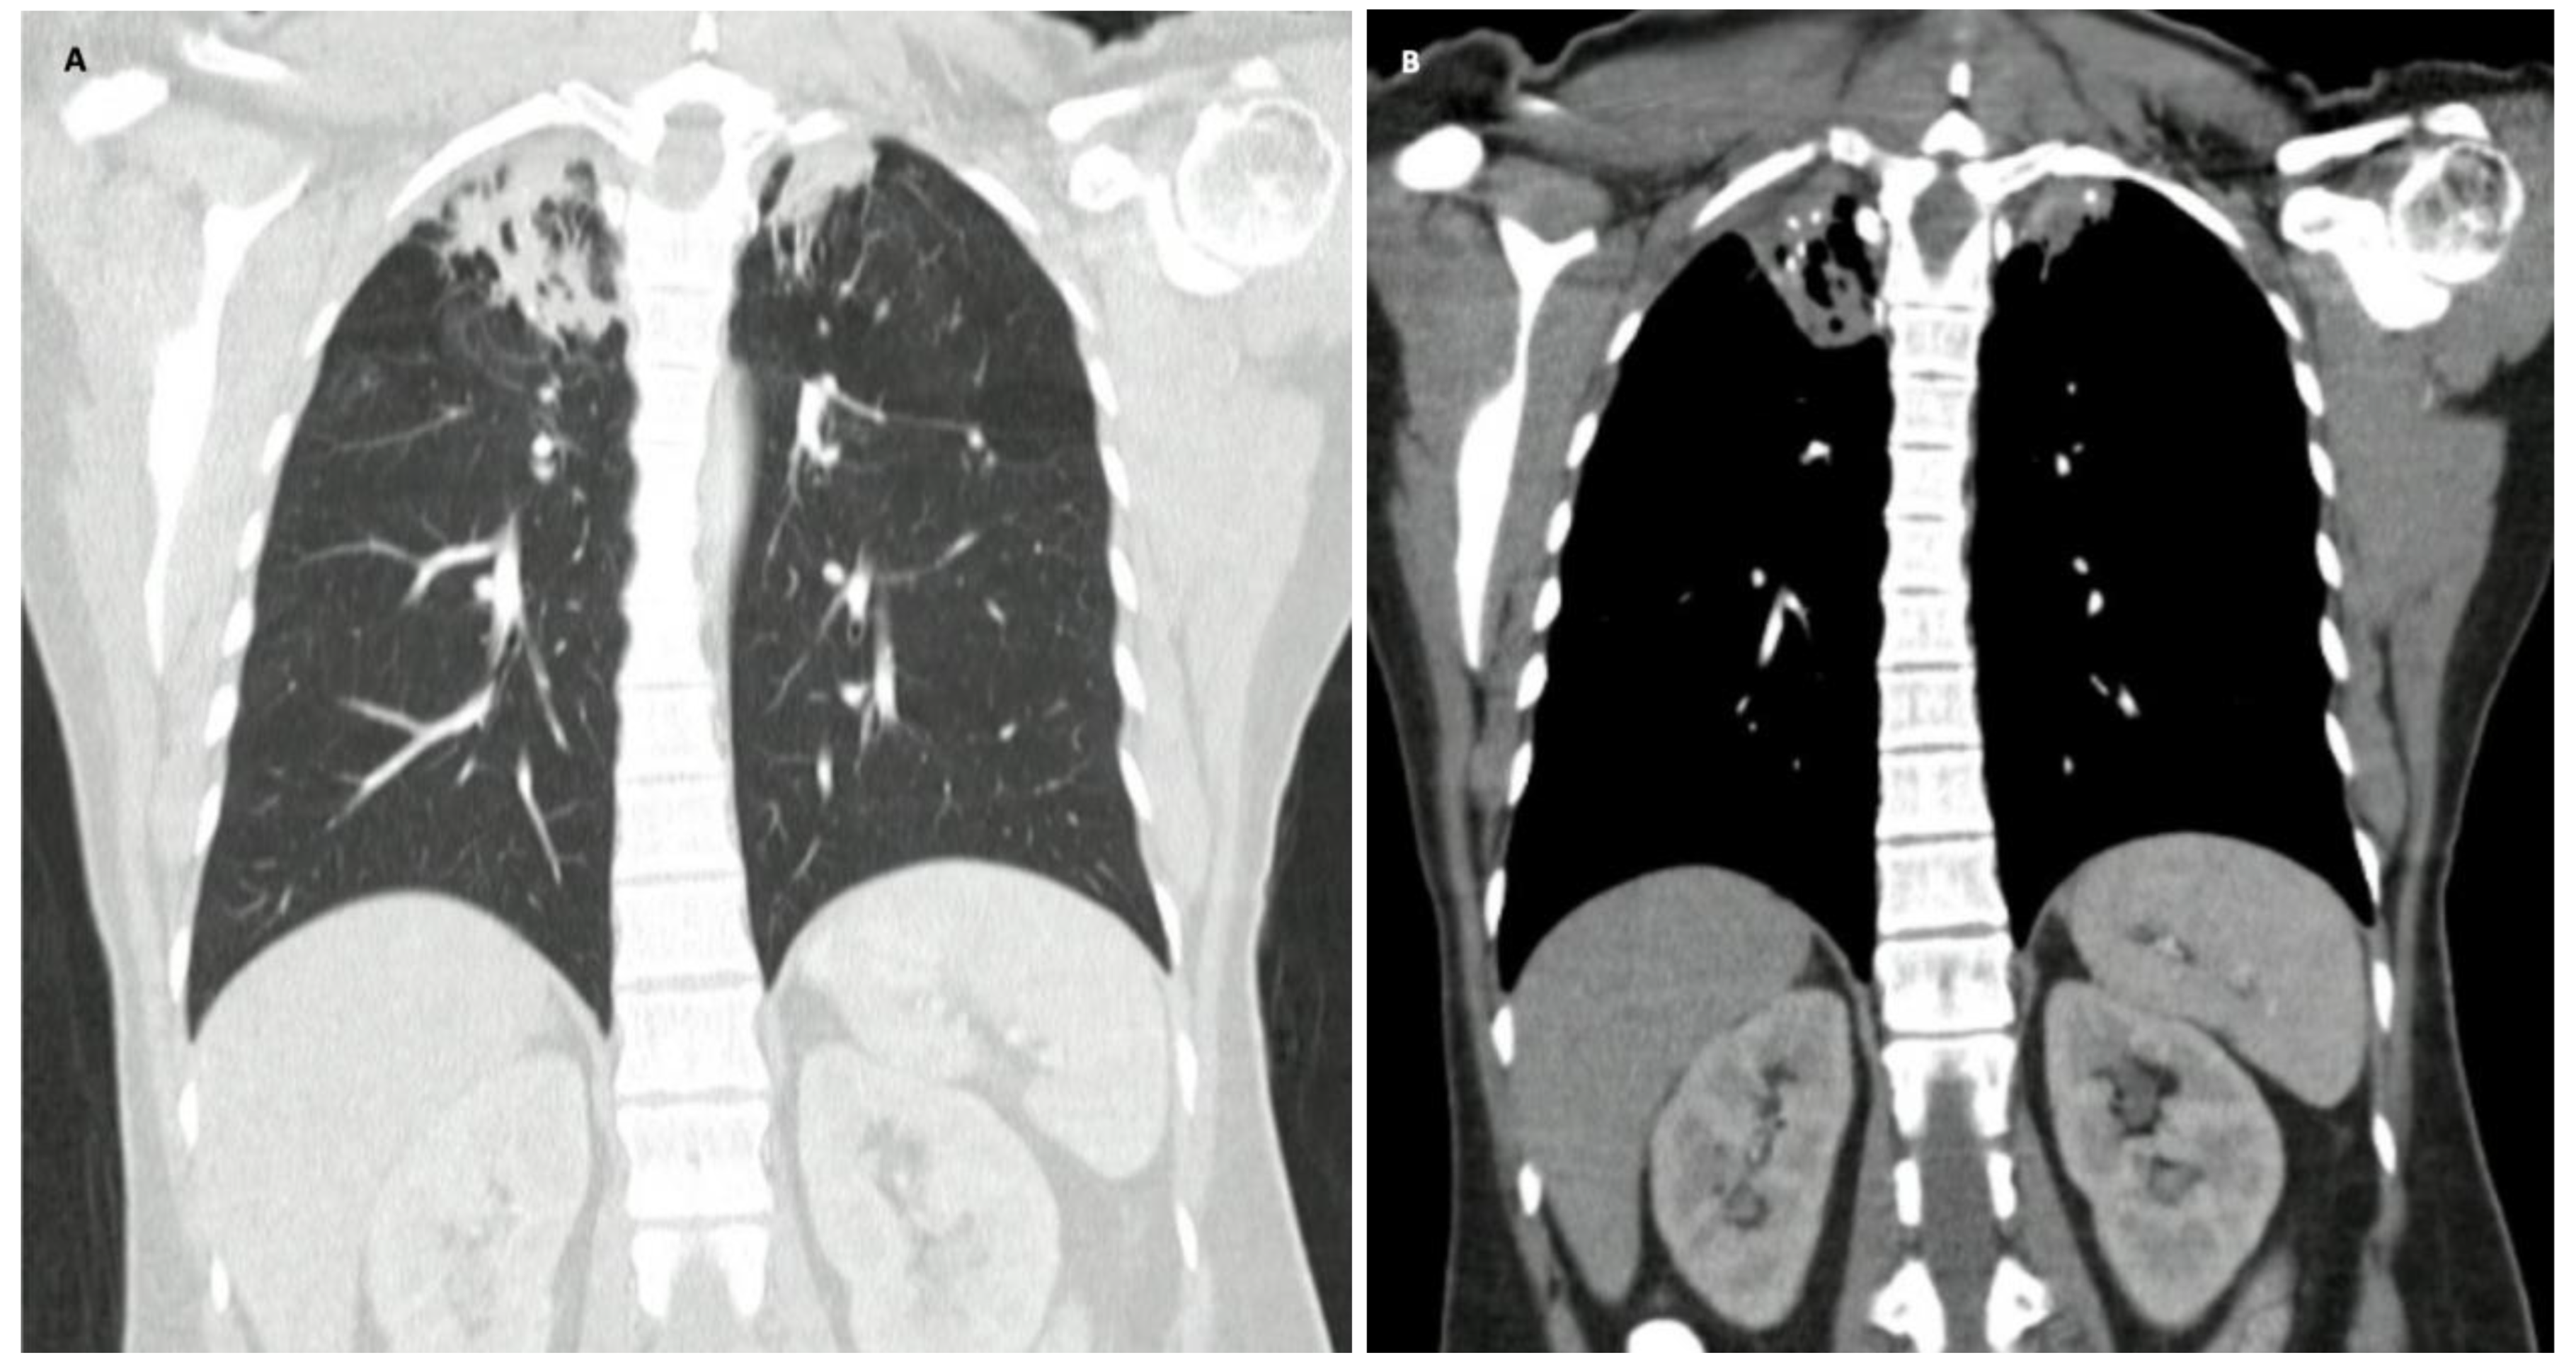

Due to weight loss, CT scans of the chest and abdomen were performed on the second day of hospitalization, documenting findings of pulmonary granulomatous disease (Figure 1). She underwent fibrobronchoscopy plus bronchoalveolar lavage (FBC + BAL) the next day due to the findings on chest CT scan.

Figure 1.

Computed tomography of the chest. A: Frontal view, pulmonary window, showing multiple opacities with signs of volume loss and distortion of the pulmonary architecture in the apical segment of the right upper lobe and apical segment of the left upper lobe, which are compatible with pulmonary granulomatous disease. B: Frontal view, mediastinal window, many calcifications, bronchiectasis and adjacent parenchymal bands can be observed in the apical segment of the right upper lobe and apical segment of the left upper lobe.